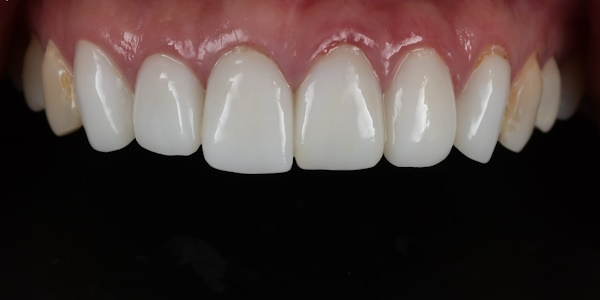

セラミック治療の治療例です。「以前、他院で治療した前歯の被せものの色味が不自然で気になる。また、被せものを入れてから歯茎が腫れるようになった。」とのことでご相談に来院されました。口腔内を確認したところ、セラミックの色が周囲の歯と調和しておらず、歯と歯茎の境目(マージン)部の適合が十分でないため、歯茎の炎症が起きている可能性が考えられました。当院にて、装着されていたセラミックの被せものを一度外し、歯茎の状態を確認したうえで、周囲の歯と自然になじむ色調のセラミックの被せものを新しく作り直しました。治療後は歯茎の腫れも落ち着き、前歯の色も周囲の歯となじみ、自然な見た目になりました。

前歯部のクローズアップ